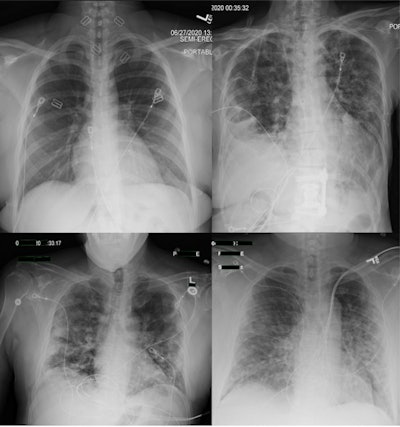

Chest x-rays may have had limited usefulness in diagnosing COVID-19 cases early in the pandemic, despite widespread use of the technology, according to a study published in the February issue of Clinical Imaging.

In a reader study, a group led by Dr. Judy Gichoya of Emory University in Atlanta evaluated radiologist performance in diagnosing COVID-19 on chest x-ray images acquired at the time patients presented in emergency departments. They found poor agreement among 10 readers from four academic institutions and that radiologist performance was ultimately nonspecific for diagnosing COVID-19.

The researchers culled RT-PCR results, clinical history, and chest x-rays of all patients tested between March 2020 and June 2020 across four academic medical centers. They included 984 RT-PCR-positive and 1,043 RT-PCR-negative radiographs. One hundred cases were read by all radiologists and 1,927 cases were read by two radiologists.

For 89 cases read by all readers, there was poor agreement for RT-PCR positive (Fleiss score 0.36) and negative (Fleiss score 0.46) exams, the researchers found. Agreement between two readers on 1,638 cases was 54.2% for RT-PCR-positive cases and 71.4% for negative cases.

Agreement was highest for RT-PCR-negative cases labeled as normal (50.4%, n = 479). In addition, reader performance did not improve with clinical history or time between chest x-ray and RT-PCR results, according to the findings.

"Emergency radiologists have nonspecific performance for interpreting COVID-19 on [chest x-ray] with a high rate of disagreement," the researchers stated.

Overall, the results are consistent with the known literature on the diagnostic capabilities of chest x-ray for the diagnosis of COVID-19 pneumonia, the researchers stated. They also reinforce expert panel recommendations against routine use of chest radiography as a COVID-19 screening test, instead highlighting it as a tool to monitor disease severity, they wrote.